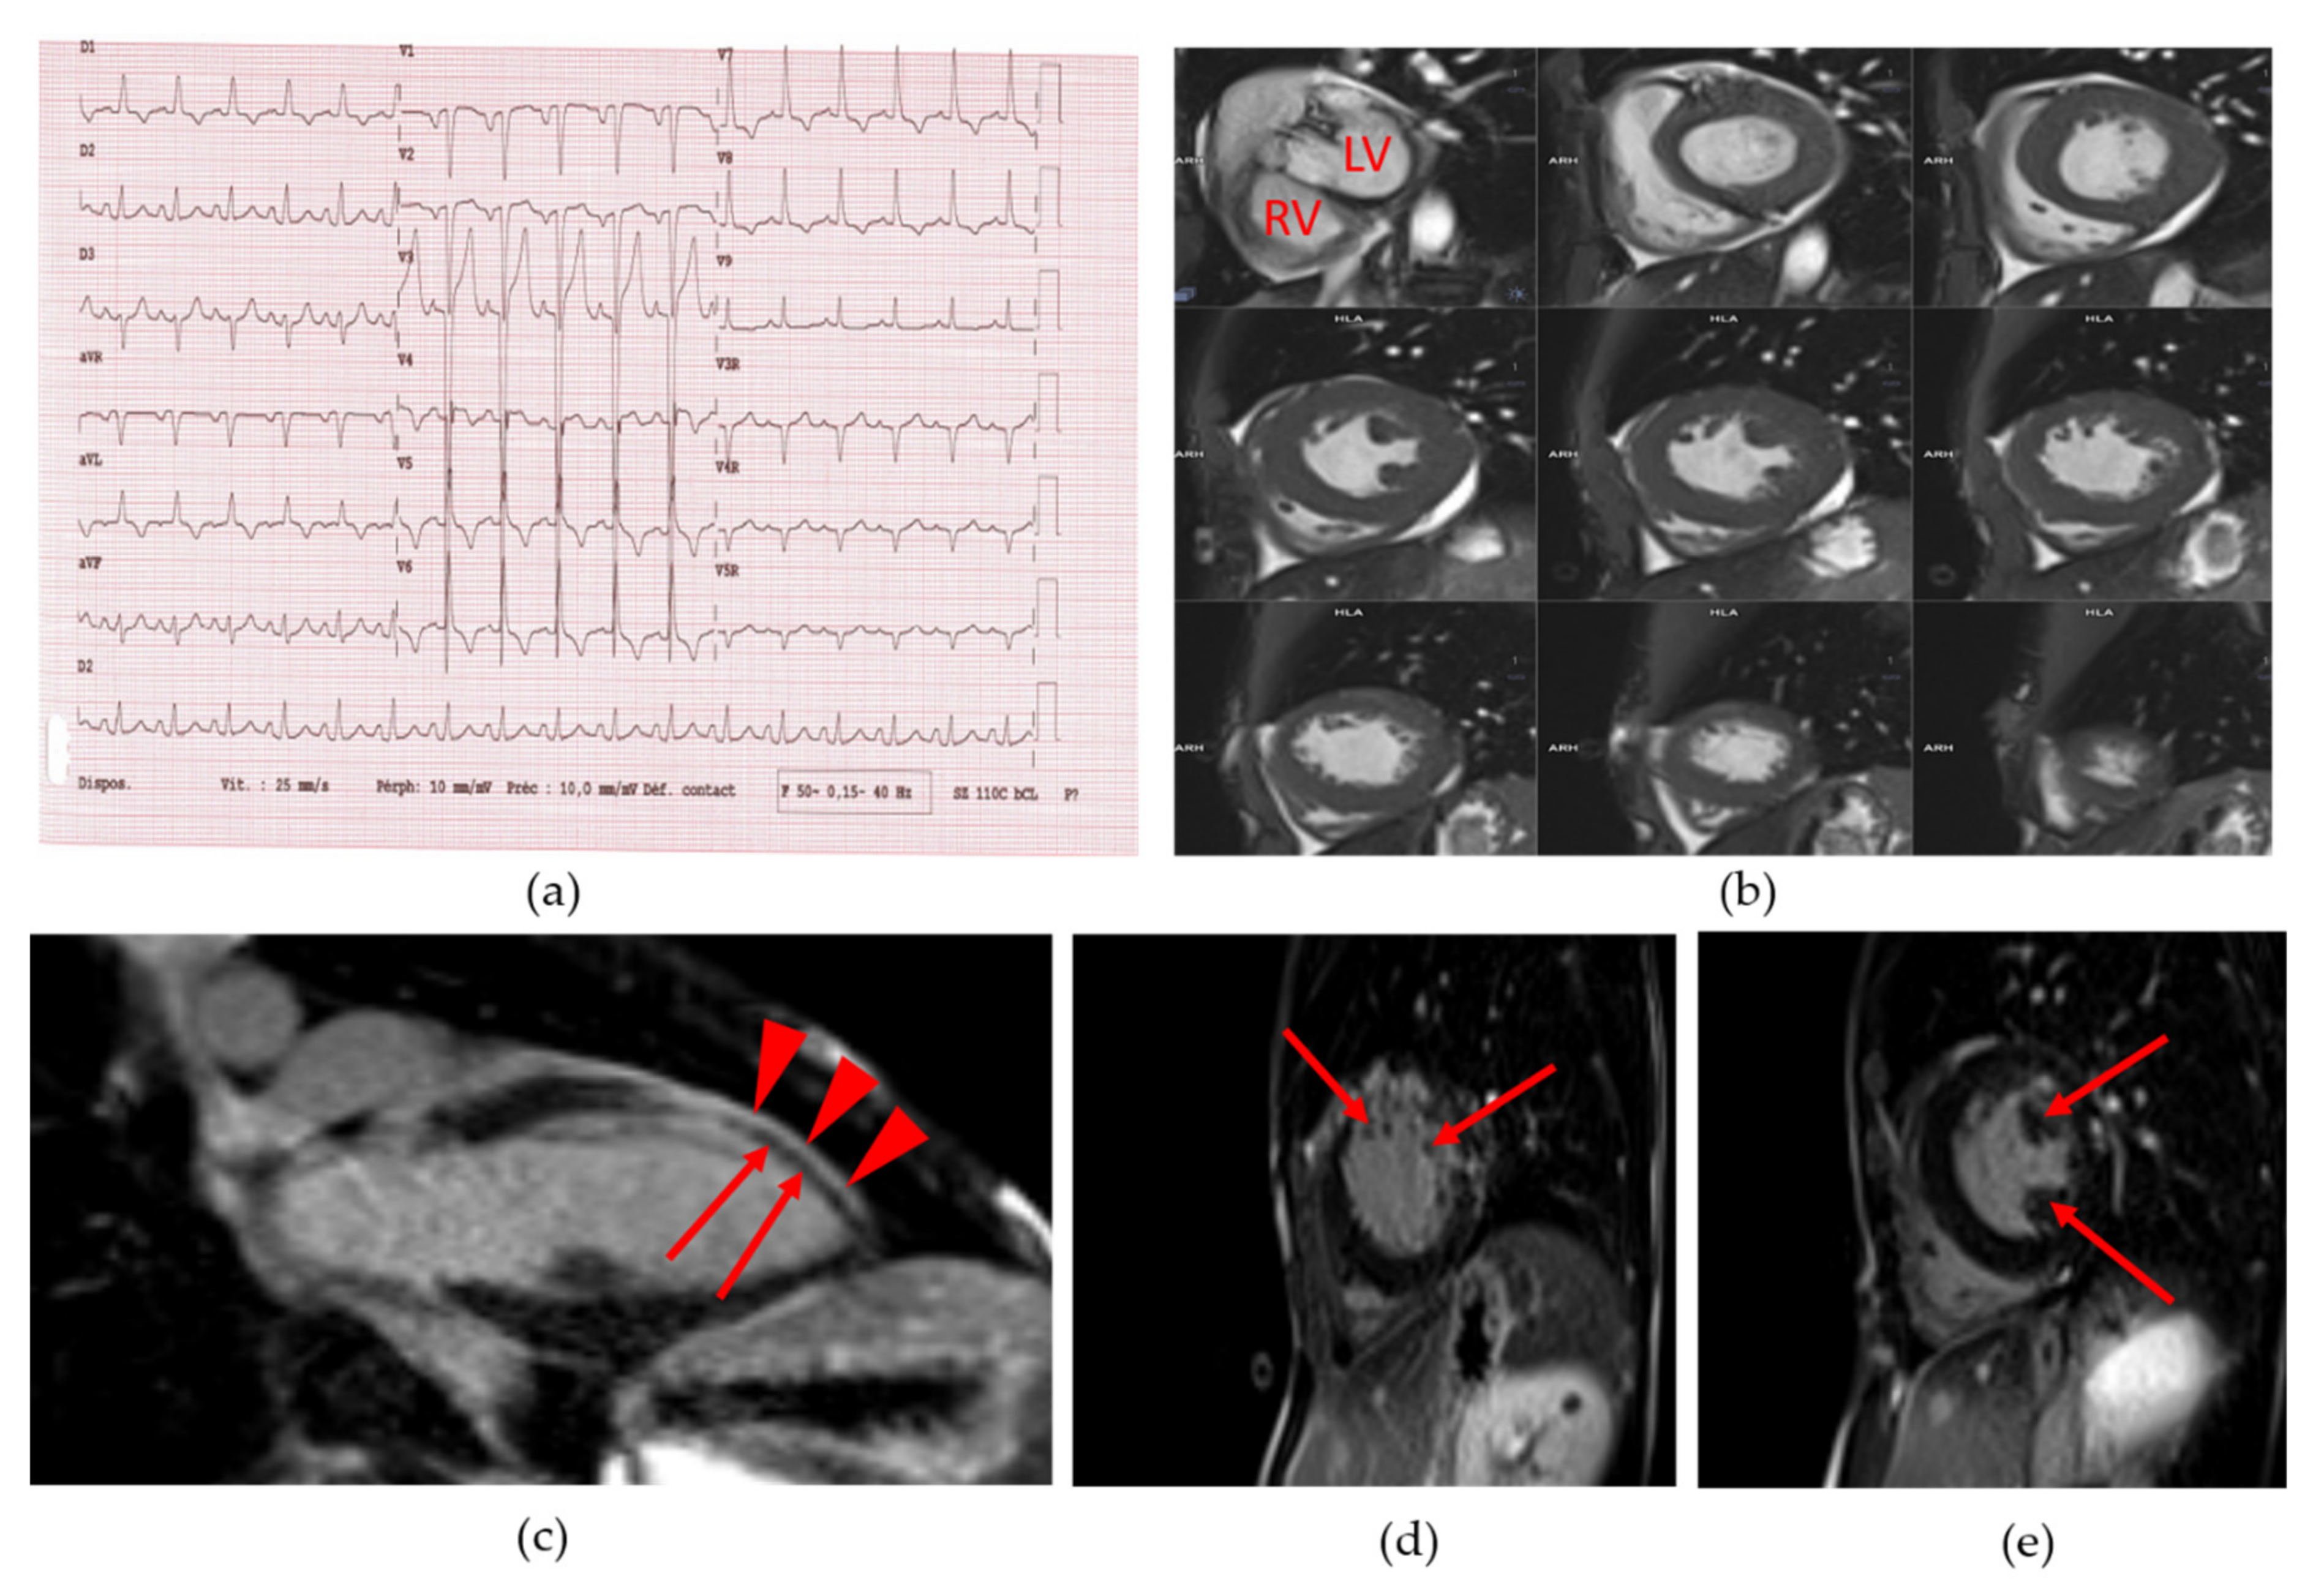

She suffered from dyspnea and had a systolic aortic heart murmur. She was a non-smoker. Her blood pressure was normal. The resting electrocardiogram (ECG) showed an incomplete left bundle branch block, left and right atrial hypertrophy, and left ventricular (LV) hypertrophy (Figure 2a). Cardiac ultrasound revealed a moderate aortic valve stenosis with mild regurgitation (aortic valve area: 0.82 cm2, i.e., 0.69 cm2/m2 of body surface, maximum aortic velocity: 2.7 m/s, gradient of aortic transvalvular pressure: 15 mmHg). The coronary computed tomography (CT) angiogram revealed extensive calcifications of ascending aorta and aortic valve, without significant coronary calcification or stenosis (Agatson score: 2). The abdominal CT angiography found major atherosclerosis and calcifications of abdominal vessels. Cardiac magnetic resonance imaging (MRI) showed a LV concentric remodeling (LV concentricity = 1.2 g/mL) with hypertrophy (septal thickness = 11 mm and LV mass index = 101 g/m2) (Figure 2b), and a LV systolic dysfunction (LV ejection fraction or EF: 42%). A diffuse hypokinesis was observed along with antero-septo-apical akinesia and wall thinning (Figure 2c) with heterogeneous late gadolinium enhancement, compatible with myocardial fibrosis [16] (Figure 2d,e and Video S1). The systematic 24-h ECG monitoring revealed malignant sustained ventricular tachycardia. The patient declined the implantation of a cardioverter-defibrillator.

Figure 2.

Patient 1 (a) 18-lead electrocardiogram (ECG) showed normal sinus rhythm with normal PR and QT intervals as well as incomplete left bundle branch bloc, left and right atrial hypertrophy and left ventricular hypertrophy; (b) Cine short axis cardiac magnetic resonance imaging (MRI) images, showing the left ventricular hypertrophy. LV: left ventricle. RV: right ventricle; (c) Cine long axis cardiac MRI image. Red arrowheads show normal gadolinium enhancement of left ventricular wall. Red arrows show defect of gadolinium staining of the antero-septo-apical myocardial region; (d) and (e): Cine short axis cardiac MRI image. Arrows show a heterogeneous late gadolinium enhancement compatible with myocardial fibrosis.

Electrocardiographic abnormalities with cardiac repolarization abnormalities have been described in HGPS, which could result from a defective cardiomyocyte connectivity due to the mislocalization of the gap junction protein Connexin 43 [30]. Alterations in lamin-mediated regulation of AKT (protein kinase B)/mTOR (mammalian target of rapamycin) pathways, which influence the expression or localization of Connexin 43, could represent another potential mechanism for arrhythmogenicity [31]. To note, prelamin A accumulation has been shown to mediate myocardial inflammation, which could contribute to acquired or genetically-determined cardiomyopathies [32]. Finally, alterations in extracellular matrix leading to fibrosis were described in laminopathies affecting adipose tissue [33,34], the vascular wall [18] and/or heart muscle [35], and could participate in multitissular complications. In that setting, the myocardial late gadolinium enhancement observed on the cardiac MRI in Patient 1 suggests evidence of myocardial fibrosis secondary to microvascular ischemia and/or primary myocardial involvement, as previously described in LMNA-related cardiomyopathies [16]. In this cardiac MRI study, late gadolinium enhancement in favor of myocardial fibrosis was observed in 15 out of 17 patients with LMNA-related dilated cardiomyopathies. To note, the patients did not presented with progeroid features but harbored LMNA variants affecting the coil 1B of the central rod domain of type A lamins, as in Patient 1 [16].

Lipodystrophy-associated progeroid syndromes due to different LMNA pathogenic variants have been described with cardiomyopathy which could be worsened by a concomitant diabetes, as noted in Patient 1 [15]. It is striking to note that coronary arteries were not significantly stenotic in this patient. Therefore, we assume that ventricular hypertrophy could be due to the conjunction of microvascular ischemic lesions worsened by diabetes, aortic valve stenosis, and primitive laminopathic muscle disease in Patient 1.

The following are available online at https://www.mdpi.com/2073-4409/9/3/765/s1, Video S1: Patient 1 cardiac MRI video (a) Cine 4-chamber view showing antero-septo-apical hypokinesia with left ventricular wall thinning and late gadolinium enhancement; (b) Cine short axis view showing left ventricular concentric remodeling with hypertrophy.